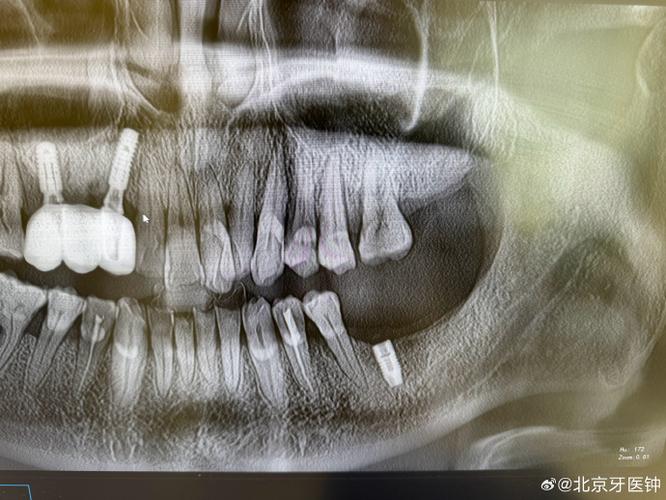

- 影像学检查: 医生会安排X光片或CT扫描来精确定位基台是在食道、胃还是肠道,以及是否有并发症。